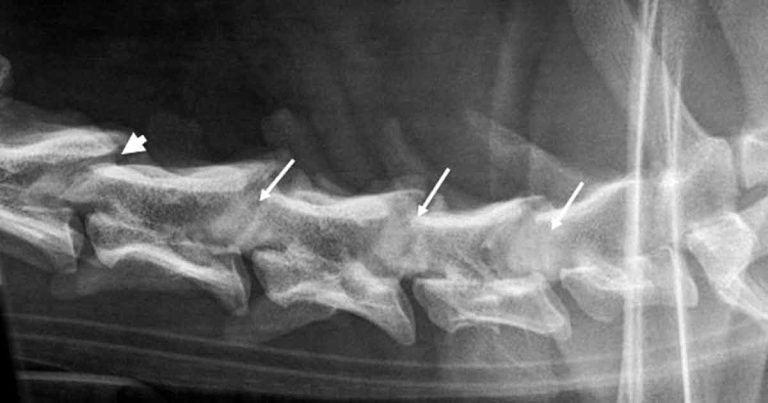

Although survey radiographs can be suggestive for DA-CSM, diagnosis can only be confirmed with myelography, CT-myelography (CT-m) or MRI1,14. Abnormalities on survey radiographs can include a narrowed or collapsed intervertebral disc space, sclerotic vertebral endplates, craniodorsal tilting or an abnormally shaped vertebral body, spondylosis deformans, and the vertebral canal appearing stenotic with the cranial orifice narrower than the caudal orifice (Figure 1)12,15,16. The latter is also referred to as a “funnel-shaped” vertebral canal16.

Survey radiographs can reveal specific abnormalities in dogs with OA-CSM, which include obliteration of the intervertebral foramina by “rounded” radiopaque structures originating from the articular processes. The normal facet joint can often not be visualised on radiographs of dogs with OA-CSM (Figure 3).